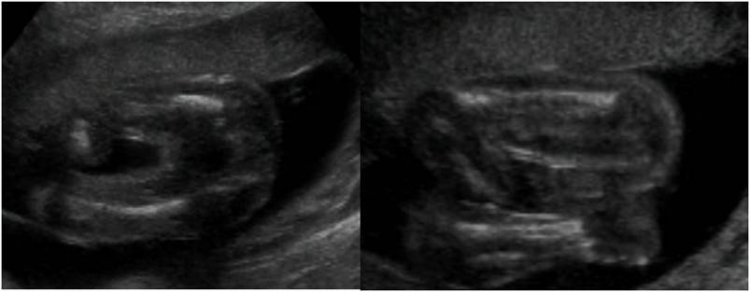

Is my baby a boy or a girl?

Is my baby a boy or a girl? Please check the picture.

Why? Would they not tell you? I have No Clue. :) But if you want a guess the last pic looked like a boy. Lol But I'm still not sure what I was looking at. I can't read a sonogram.